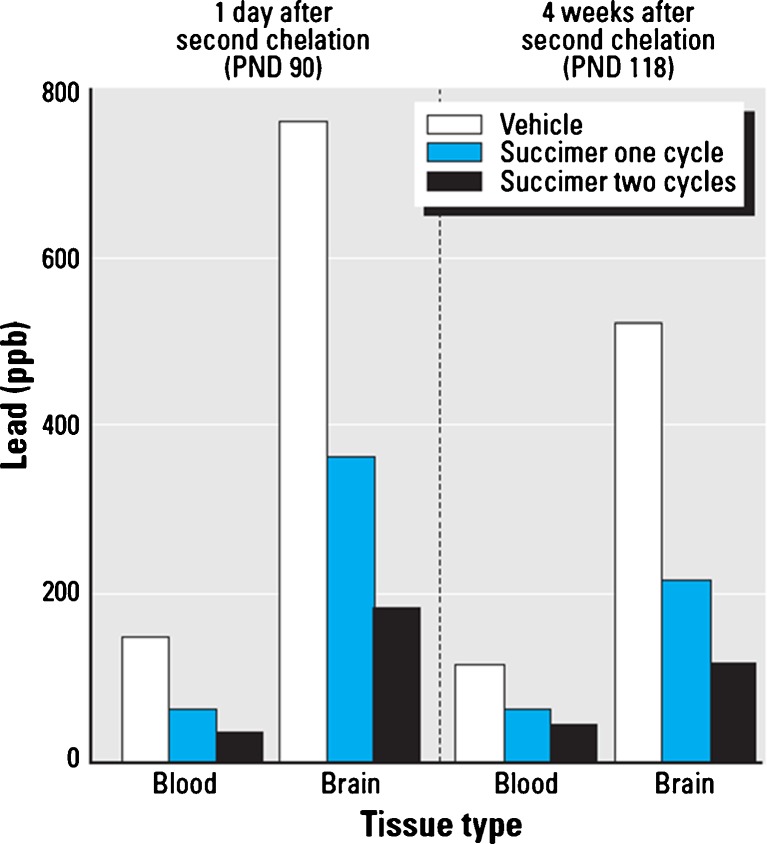

We then conducted a rodent study to follow up the adult primate study to evaluate the efficacy of repeated chelation regimens to reduce blood and brain lead levels [14]. The rodent study utilized a 3 × 3 factorial design, with three levels of lead exposure (none, low, or high) and three levels of succimer treatment (none, one, or two succimer regimens). Animals were exposed to lead orally from the first day of life until postnatal day 40, followed by either one regimen of succimer chelation (PND 40–61) or two regimens, with the second regimen from PND 68 to 89. In each of these succimer regimens, the daily oral succimer dose over treatment days 1–7 was 50 mg/kg/day, followed by 25 mg/kg/day over treatment days 8–21, divided into two oral doses per day.

The results show that there were significant reductions in both blood and brain lead levels with succimer treatment, compared to vehicle, in this rodent model (Fig. 12). Specifically, blood and brain lead levels in animals treated with vehicle, one cycle of succimer or two cycles of succimer, and then evaluated either 1 day or 4 weeks after the second regimen ended show that two successive chelation regimens are significantly more efficacious at reducing brain lead levels than a single regimen. By comparison, the additional benefit of two versus one chelation regimen for reducing blood lead levels was not nearly as striking (Fig. 12).

Fig. 12.

Relative benefit of none, one, or two succimer chelation regimens for reducing blood and brain lead levels in rats. Data highlight the additional benefit of a second regimen of succimer treatment (vs. one regimen and vehicle treatments) in reducing blood and brain lead levels in rats, as a function of time since the second regimen ended. Data from Stangle et al. [14]. [Reproduced with permission from Environmental Health Perspectives]

Overall, these non-human primate and rodent study results indicate that blood lead levels may not accurately reflect changes in brain lead with chelation, and that reductions in brain lead levels lag significantly behind reductions in blood lead levels. They also indicate that brain lead levels may not be readily reduced with succimer chelation treatment when compared to the cessation of lead exposure alone, unless a sufficiently prolonged or aggressive chelation regimen(s) is used.